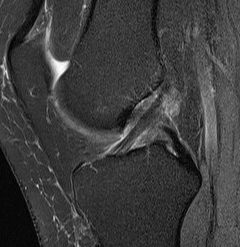

Torn ACL on MRI

Findings

- high signal intensity / oedema in ACL, especially acutely

- unable to identify continuous fibres from tibia to femur

- loss of taut, straight line of fibres

Sagittal TI MRI with no femoral attachment

Sagittal T2 MRI with midsubstance ACL tear Sagittal T1 MRI with midsubtance ACL tear

Sagittal MRI with complete ACL rupture